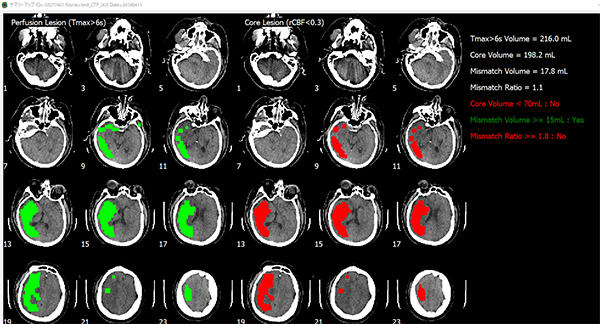

同製品を使った,CT画像の解析例

脳画像解析プログラム PMAneo(以下 PMAneo)は,MRI拡散強調画像から低ADC値領域を計測,またMRIまたはCT灌流画像からCBF,CBV,最大遅延時間を計測し,脳血流低下領域の容積およびこれらの差と比を算出,表示する,全自動脳画像解析ソフトウェア。

PMAneoは,虚血コアと低灌流領域に相当する体積及びミスマッチの自動解析を数分で行う脳画像解析プログラム。

急性期脳梗塞に対する血管内血栓回収療法の適応患者の選択の支援やワークフロー改善に向けて,使用されることを想定している。